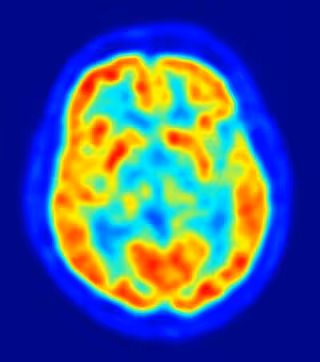

Una nueva investigación financiada por los Institutos Nacionales de la Salud de Estados Unidos ha ofrecido pistas sobre cómo el autismo afecta al cerebro, mediante el estudio de una forma rara de la enfermedad, puramente genética, que afecta a menos de 20 personas en todo el mundo, según los resultados que publica en su último número la revista 'Nature Medicine'.

En concreto, los investigadores han convertido células de piel de los pacientes en neuronas para descubrir qué es lo que falla en el cerebro con el síndrome de Timothy. Los niños afectados por este trastorno a menudo muestran síntomas del espectro autista, junto con una amplia constelación de problemas físicos.

Las anomalías incluyen cambios en la composición de las células en la corteza cerebral, la estructura más grande del cerebro en los seres humanos, y de las neuronas que segregan dos mensajeros químicos claves. Por otro lado, las neuronas que realizan conexiones de larga distancia entre los hemisferios del cerebro tienden a ser escasas.